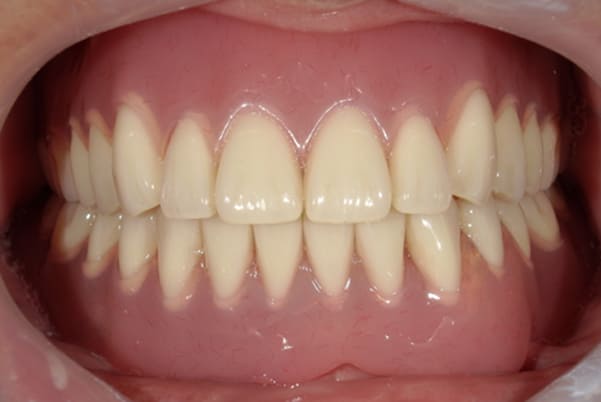

初めての入れ歯が総入れ歯の場合は、大きな違和感を感じられる方が多いですが、上顎に金属を用いた入れ歯にすることで、厚みを薄くし違和感を抑え、お食事での温熱も感じられるようになりました。

下の総入れ歯は外れやすいため大きな虫歯はありましたが、虫歯治療を行い、根のみ残せた2本の歯に磁石を利用することで歌われた際も外れない入れ歯の設計としました。

下顎は舌があるため、上顎と比較すると総入れ歯の場合、外れやすい傾向があります。患者様はまだお若く、お肉がお好きだったとのこと、またお歌もご趣味とのことで、ご相談の上、なるべく外れない設計としました。

磁石を用いた入れ歯の設計により上下の入れ歯は、お食事やお歌を歌われ大きなお口を開けても外れない状態が可能になりました。

当初、ハンバーガーを召し上がりたいと仰っていましたが、今ではステーキも召し上がられ、カラオケでも入れ歯は外れず、滑舌が全く変わったと喜んで下さりました。